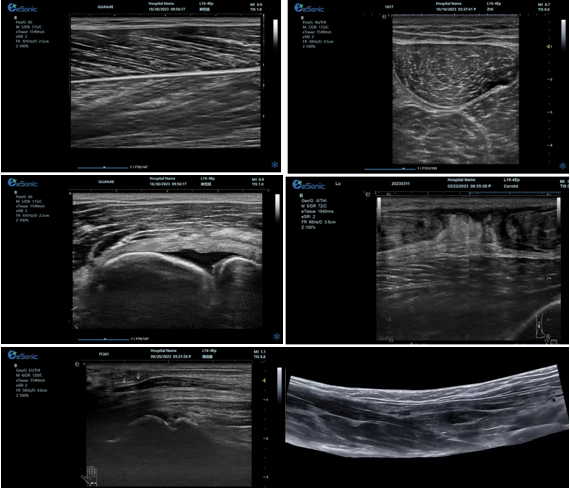

优异的图像质量

肌骨超声精确评估解决方案:

1、肌肉、肌腱、韧带专业评估

2、骨及软骨、滑膜及滑囊专业评估

3、神经病变及相关疾病临床应用

4、超声引导下可视化穿刺治疗

5、超声引导下可视化冲击波治疗